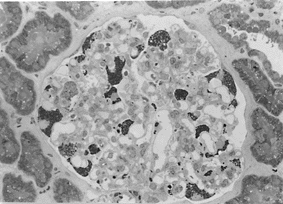

写真−1 トルイジン青染色

写真−2 糸球体上皮細胞のライソゾーム内にオスミウム好性、大小多数の同

心円層状封入を認める。

BM:基底膜 bar=5μm

腎を含む多くの組織の細胞質内に、neutral glycosphingolipidsが蓄積し病変を起こす。腎病状では、ヘミ接合体の男性では、20〜30歳代で血尿と軽度の蛋白尿が出現し、50歳代には多くが末期腎不全へ進行する。ヘテロ接合体の女性では、α-galactosidaseAの活性の程度により、無症状のものからヘミ接合体男性と同程度の臨床症状を呈するものまでさまざまであるが、一般にヘミ接合体男性に比較し症状は軽度で、予後も良好である。組織学的には、糸球体の変化が最も顕著であるが、尿細管、血管にも病変はみられる。パラフィン包埋標本では糸球体上皮細胞は腫大し空胞化する。空胞の大きさは小さく一様で上皮細胞は“honey comb”様の所見を示す。しかし、この空胞は電顕ブロックのトルイジン青染色標本では、オスミウム好性を示し細胞質内の顆粒として認める(写真−1)。

病初期には糸球体はほぼ正常であるが、進行に伴い硬化が進む。電顕的には、細胞のライソゾーム内に大小多数の高電子密度の、タマネギ様の同心円層状封入体(myelin figures)がみられる。この封入体は上皮細胞に最も多くみられ(写真−2)、病初期には糸球体基底膜は正常であるが、病気が進行すると、動脈、細動脈病変に付随し糸球体の肥厚、蛇行が起こってくる。